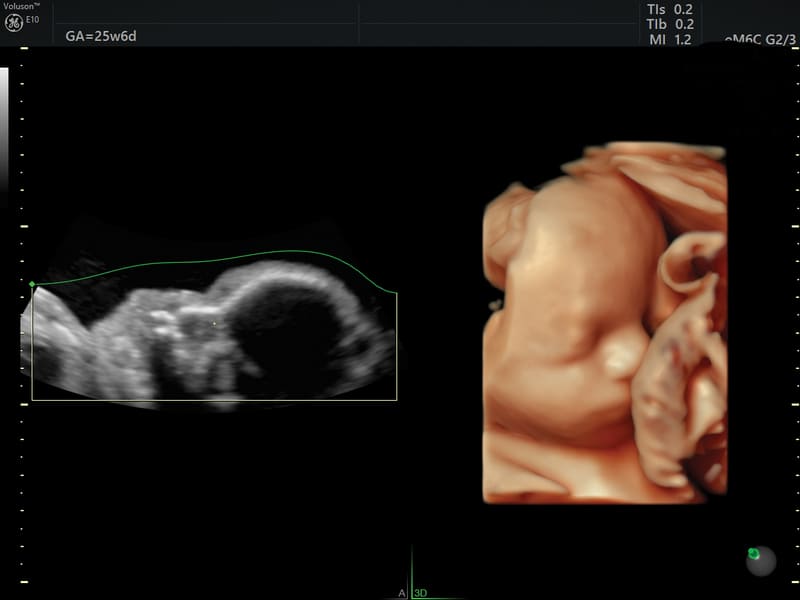

Nuova sonda convex volumetrica a matrice elettronica eM6C G3: questo trasduttore si distingue dalle sonde tradizionali per l’assenza di parti meccaniche in movimento: utilizzando lo steering elettronico di oltre 8000 elementi in matrice convessa consente di eseguire acquisizioni ultraveloci mantenendo una qualità d’immagine eccezionale e, grazie alla modalità “biplane”, permette la visualizzazione in tempo reale di due piani ortogonali in real time, migliorando il workflow e la riproducibilità dell’acquisizione

HDlive™: tecnologia di rendering del data set volumetrico che genera immagini incredibilmente realistiche del feto.